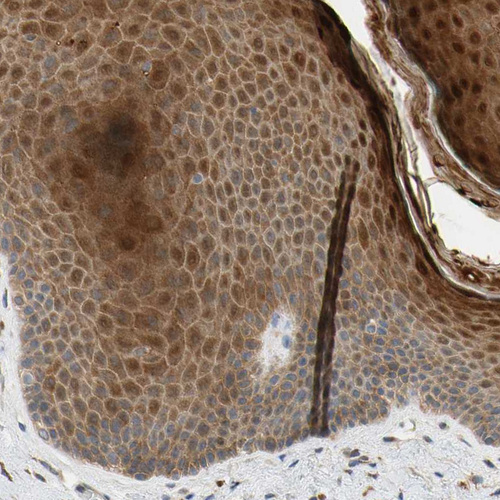

Immunohistochemical staining of human placenta shows moderate cytoplasmic positivity in trophoblastic cells.